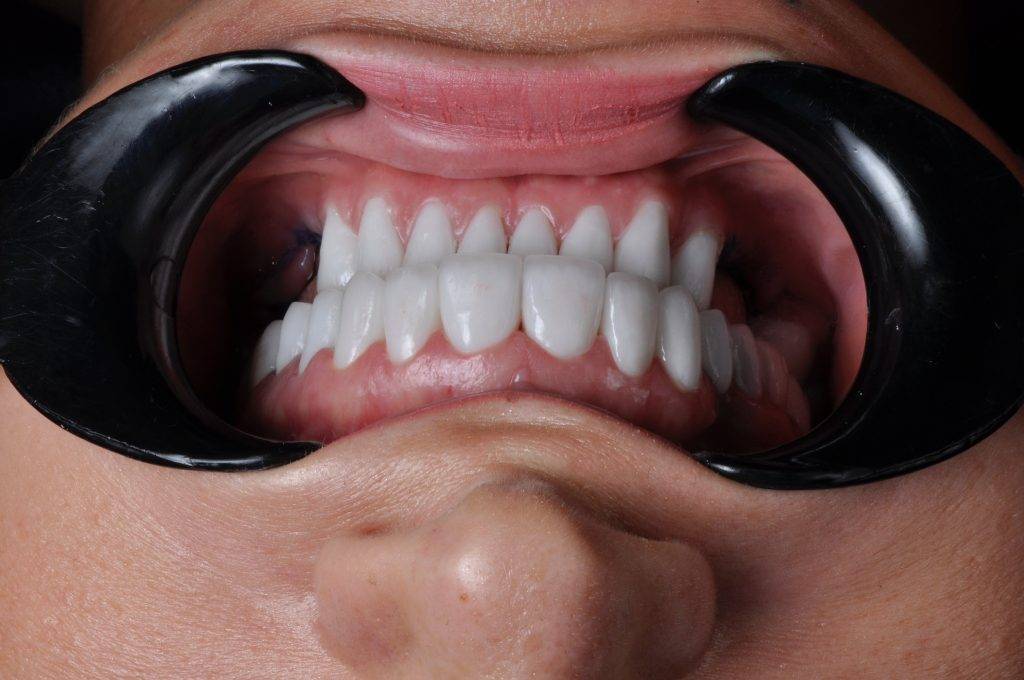

Unsere Galerie

Über 1000+ glücklichen Patienten

Glückliche Kunden Zahnmedizin